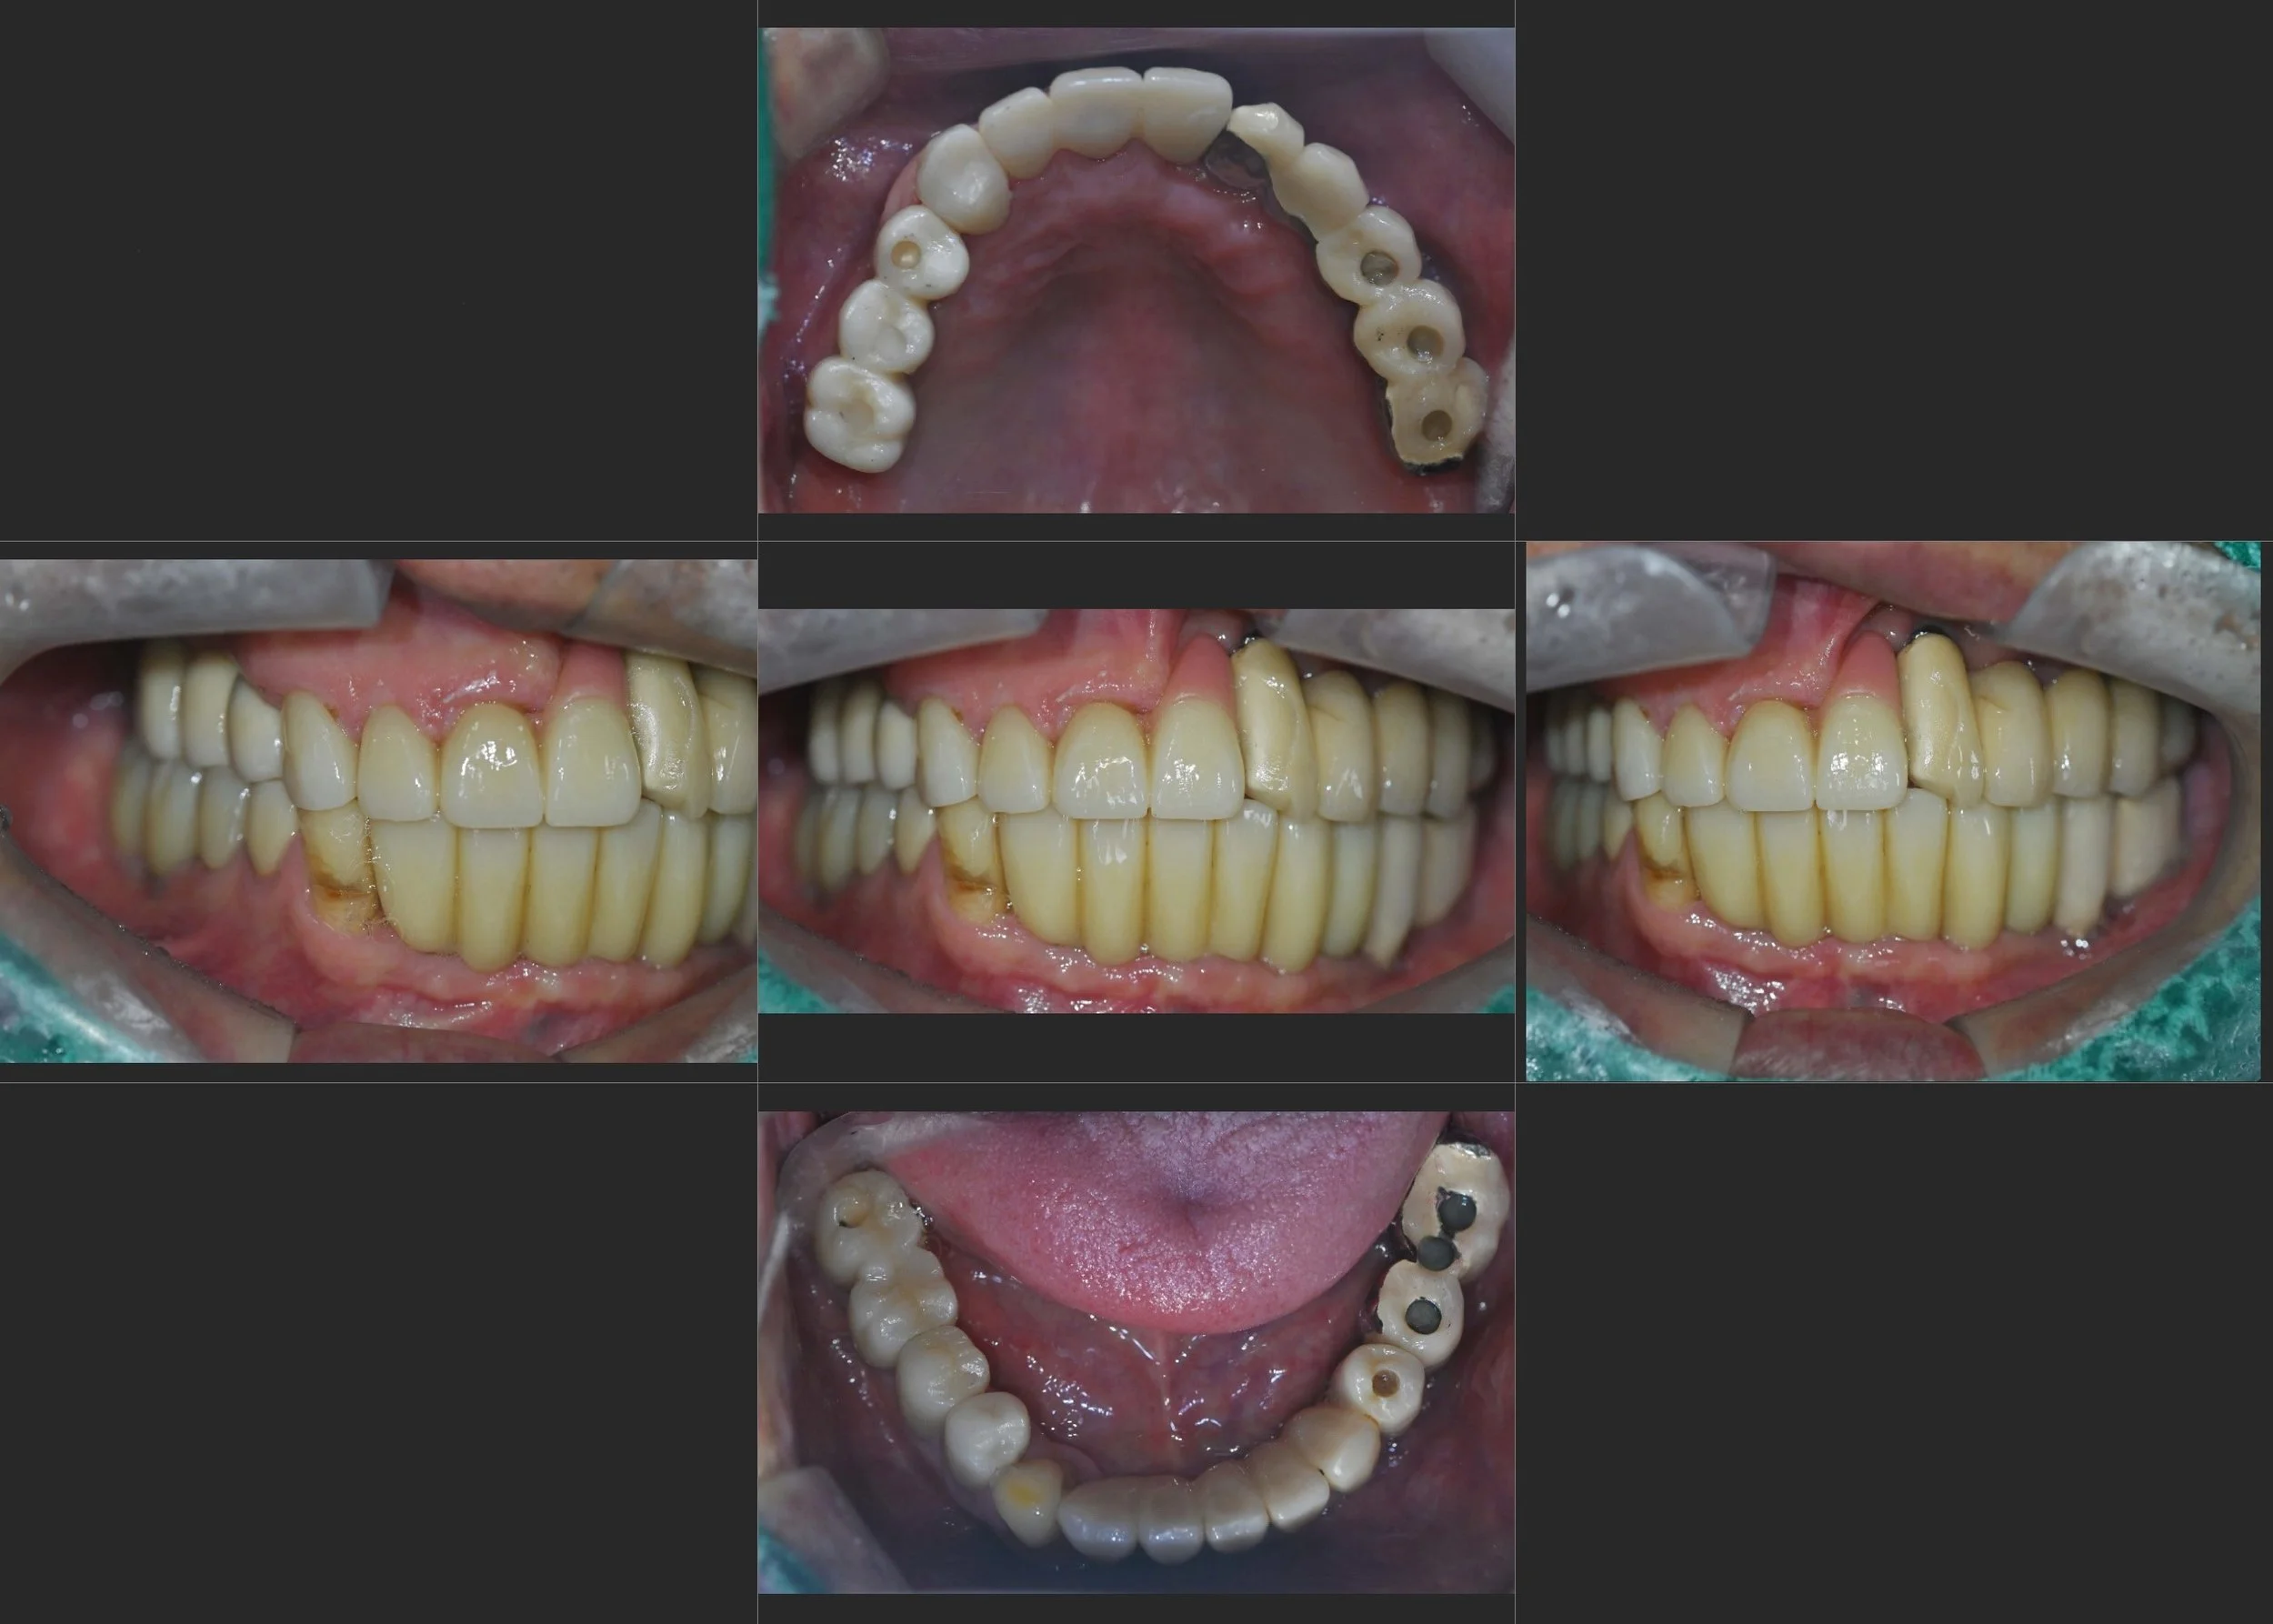

INTRA ORAL - AFTER

2. Priority Segment Delivery: The right posterior implant-supported bridges and the anterior aesthetic crowns were completed first. This restored immediate chewing function on one side and significantly improved the patient’s facial aesthetics.

3. Compromised Left Occlusion (Intentional): Following the patient's request, the left posterior occlusion was temporarily left in its current state. While this resulted in a non-ideal bilateral balance for the time being, the right and anterior segments were engineered to withstand the loads until the left-side surgery is performed.

The patient is highly satisfied with the improved aesthetics and the ability to function on the right side, with a clear understanding and plan for the final phase of his full-mouth journey.